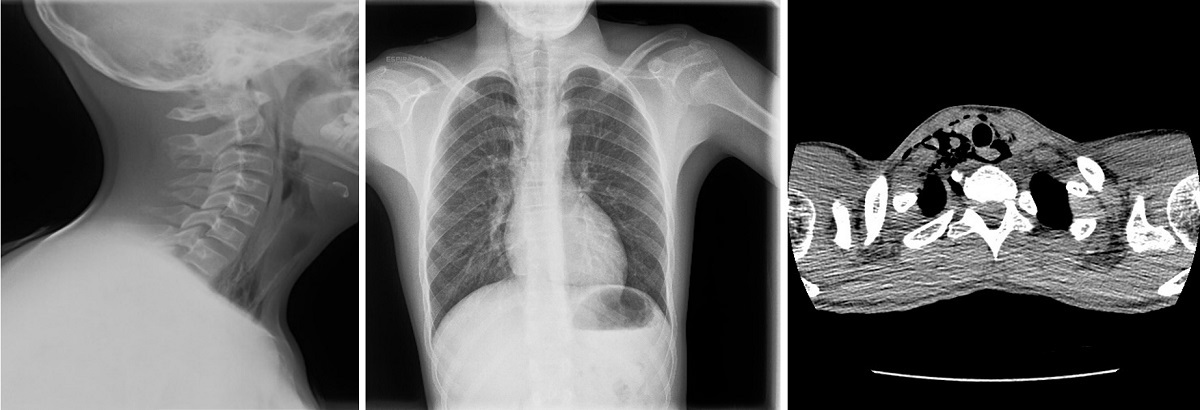

The vital signs were in the normal range. There was subcutaneous emphysema in the right submandibular area. The rest of the physical examination was normal. In the soft-tissue neck and chest radiographs, there were hyperlucent areas in the right superior mediastinum associated with the continuous diaphragm sign and subcutaneous emphysema in the right side of the neck. A neck and chest CT scan revealed anterior, medial and posterior pneumomediastinum extending cranially into the soft tissues surrounding the trachea and oesophagus toward the right carotid sheath and the right retropharyngeal space (Figure 3). The findings of the ECG, flexible fibreoptic laryngoscopy examination and blood tests were normal. The patient remained in hospital for 3 days under continuous vital sign monitoring and did not require active treatment at any point. He was evaluated in the paediatric cardiology and paediatric pulmonology departments, and there were no significant findings or events and no recurrences.

| Figure 3. Case 5. Male adolescent aged 13 years referred to the emergency department by his primary care paediatrician for evaluation of right cervical and central chest pain of 5 hours’ duration associated with dyspnoea and difficulty swallowing. Soft-tissue neck and chest radiographs with hyperlucent areas in the right superior mediastinum, continuous diaphragm sign and subcutaneous emphysema in the right side of the neck. Neck and chest CT scan revealed anterior, medial and posterior pneumomediastinum extending cranially into the soft tissues surrounding the trachea and oesophagus toward the right carotid sheath and the right retropharyngeal space |

![]() |